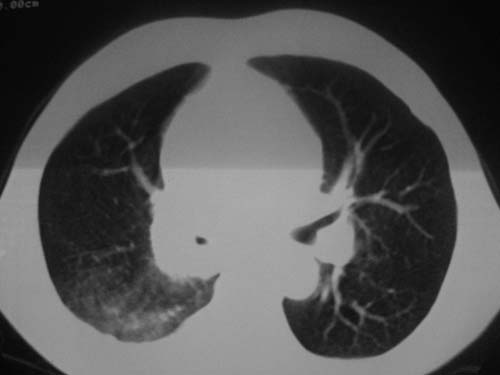

以下是引用科室第一人在2010-3-25 20:30:00的发言:[br]1:纵膈肿瘤性病变,恶性胸腺瘤可能性大伴纵膈右肺门淋巴结转移,右侧胸腔积液。[br]2:右侧肺门肿瘤性病变,纵膈淋巴结转移,右侧胸腔积液。右下叶转移。

以下是引用子期在2010-3-25 21:00:00的发言:[br]先考虑右中央型肺癌伴转移。

以下是引用江广1996在2010-3-25 22:49:00的发言:[br]通常肺癌向纵隔转移多见,纵隔肿瘤向肺内转移少见(有的表现为向肺内侵润)。本例以一元论考虑:右中心型肺癌并纵隔淋巴等多处转移。[br][br][本贴已被 江广1996 于 2010-3-25 22:50:07 修改过]

以下是引用yangyudong333在2010-3-26 6:43:00的发言:[br]“冰冻纵膈”,考虑纵膈淋巴瘤伴肺内及胸膜侵润。